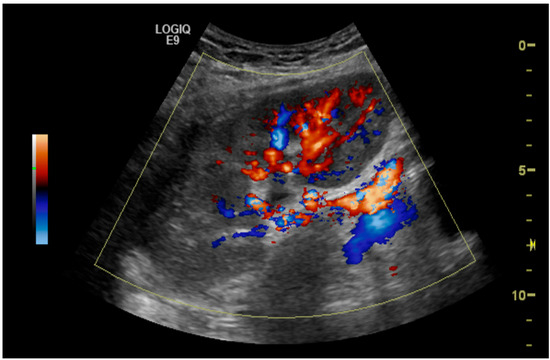

Clinical Utility of Duplex Ultrasonography in the Recognition of Transplant Renal Artery Stenosis: A Single Center Experience

2. Methods and Materials

- More than 50% renal artery stenosis on initial Duplex ultrasonography;